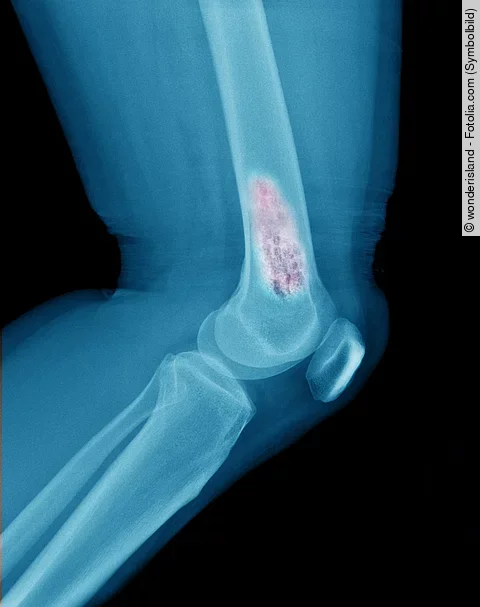

Knochenmetastasen bei Prostatakrebs: Alpha-emittierende Radioisotope verbessern Gesamtüberleben

Bislang existiert nur eine einzige Phase-3-Studie, welche den Vorteil des alpha-emittierenden Radioisotopes Radium-223 im Vergleich zur Standardtherapie gezeigt hat. Doch gibt es einen Unterschied zwischen alpha- und beta-emittierenden Radioisotopen bei der Therapie des metastasierten, kastrationsresistenten Prostatakarzinoms?